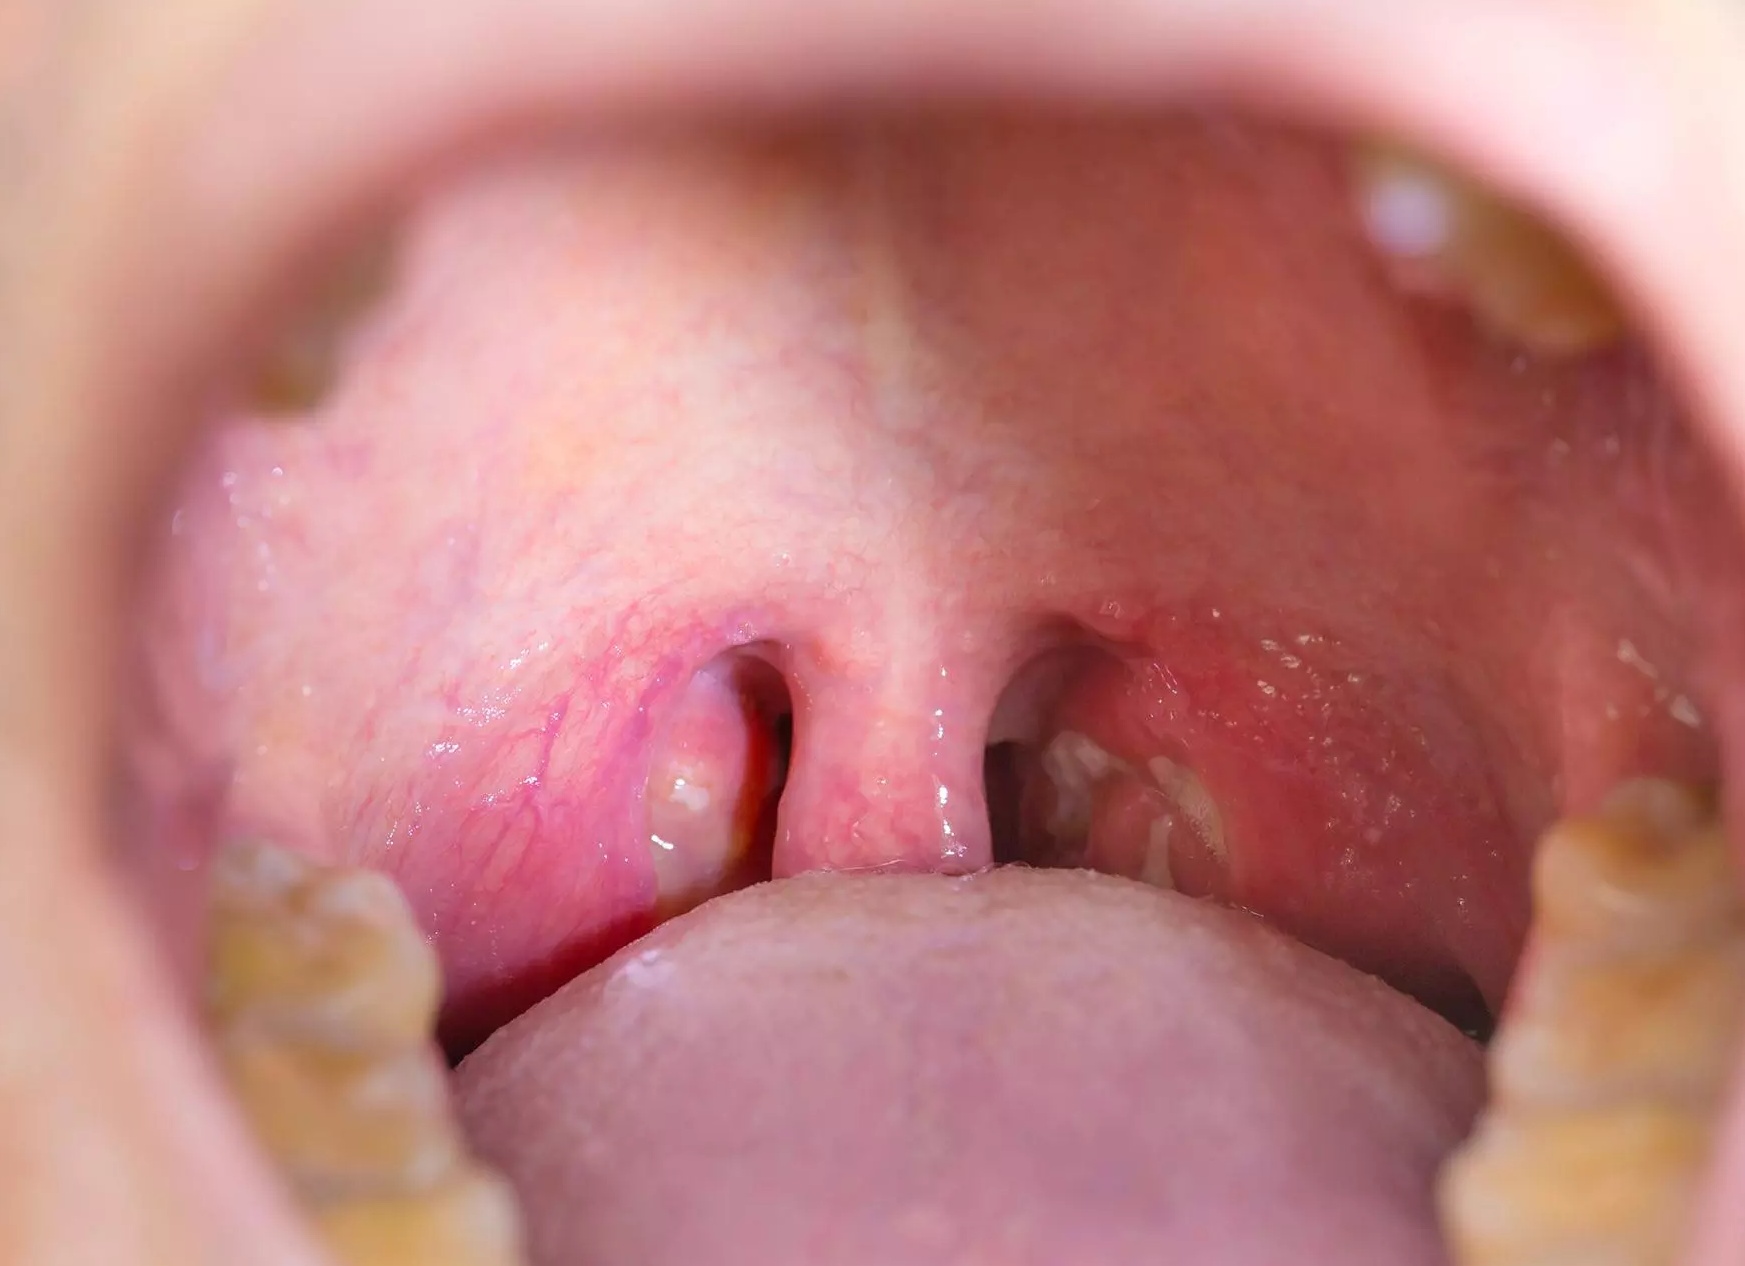

На фото — ангина